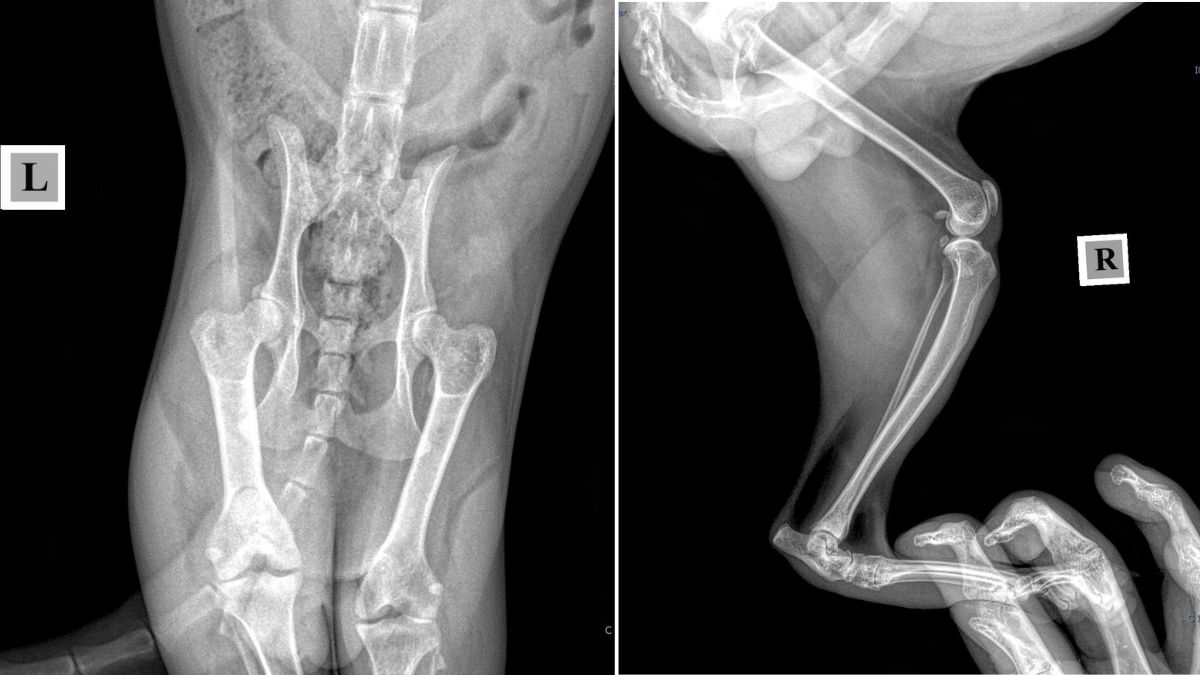

Попри те, що пані Вікторія безмежно вдячна небайдужим благодійникам, які допомагають закривати поточні борги, потік нових викликів не вщухає. Жінка каже, що останній візит до клініки приніс різні новини: якщо у собаки Діни з пластиною в лапці все добре і проблема виявилася лише дерматологічною, то ситуація з іншими підопічними значно складніша. У пса Каспера виявили задавнену травму та проблеми з нирками, що потребуватиме тривалого догляду. Проте найважчим лишається стан Сімби — хірургічне втручання для котика є життєво необхідним.